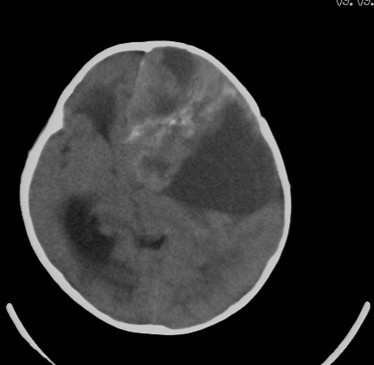

男  4岁  家长觉得反应迟钝来检查发现。

病史?脑疝都形成了,这家长也太马虎了。

感冒后发现反应迟钝来检查

考虑脑占位并出血,脑疝形成。

考虑左侧颞顶叶占位并出血,脑疝形成

有出血,考虑神经母细胞瘤或星形细胞瘤,胶母好发老年人,儿童罕见,中颅窝的是扩大的侧脑室颞角吧不是囊肿吧。脑白质密度减低,建议mr.

先天性疾病.小脑是正常的,左侧大脑半球发育不良伴有脑肿瘤形成,脑积水.名堂真多。建议mri

考虑左侧颞顶叶占位并出血,脑疝形成!

考虑左侧颞顶叶占位并出血,脑疝形成!梗阻性脑积水

考虑左侧颞顶叶占位并出血,脑疝形成,梗阻性脑积水。

1)考虑左侧额颞顶叶肿瘤并卒中;建议行进一步检查。2)大脑镰下疝,左侧颞叶沟回疝。3)脑积水(梗阻性)。

支持考虑左侧颞顶叶占位并出血,脑疝形成,梗阻性脑积水。

左侧颞顶叶占位并出血,脑疝形成

考虑左侧额颞顶叶占位并出血,脑疝形成,梗阻性脑积水。